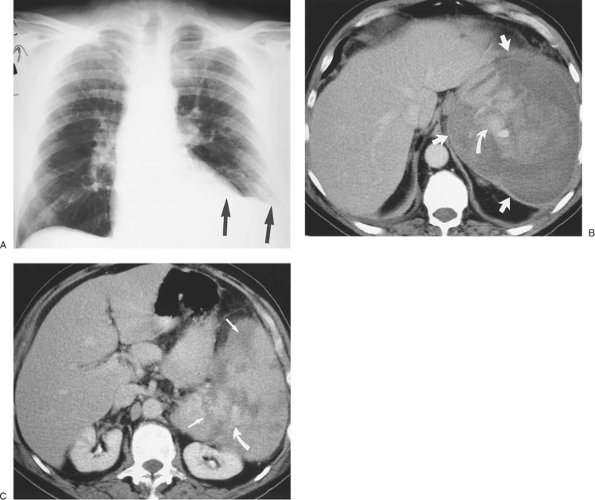

FIGURE 9-42. Elevated diaphragm secondary to subdiaphragmatic splenic hematoma. A: AP upright chest radiograph of a 68-year-old man with left flank pain and chronic lymphocytic lymphoma shows elevation of the left hemidiaphragm (arrows). B: CT shows a large subcapsular splenic hematoma (straight arrows). The high-attenuation material within the hematoma represents acute bleeding (curved arrow). C: CT at a level inferior to (B) shows multiple low-attenuation areas within the spleen from spontaneous splenic rupture (straight arrows) and high-attenuation material from acute bleeding (curved arrow).